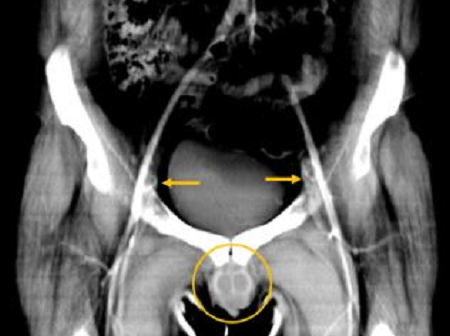

O painel A mostra uma reconstrução tomográfica computadorizada pré-operatória da extensão da lesão; o B mostra o enxerto; o C mostra o enxerto antes do procedimento, juntamente com imagens clínicas dos dias 8, 15 e 340 do pós-operatório. (Imagem: Redett et al., NEJM, 2019)